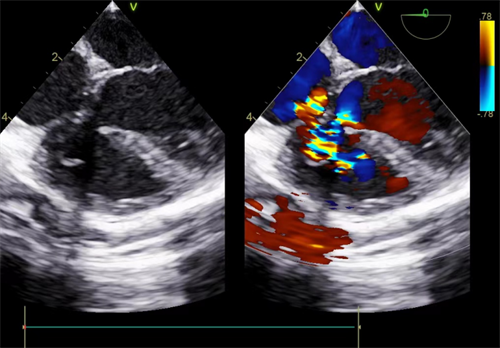

室间隔缺损(VSD)是一种由于胚胎期室间隔发育不良而引起的左右心室之间存在交通,产生室水平分流的先天性心脏病。VSD是最常见的先天性心脏病,占先天性心脏病的20%-30%。封堵器作为介入治疗的植入物,用于治疗室间隔缺损(VSD)已在临床得到广泛的应用。

术前室缺

室间隔封堵器由镍钛金全网密集编制而成的自膨性双盘结构,可在超声引导下通过一根导管将封堵器准确的放到缺损部位,将其堵塞。相对于开胸手术治疗而言,介入传统封堵器治疗有创伤小、恢复快、并发症少等优点。但是植入人体的封堵器是由镍钛金丝编制而成的,将永久存在人体内,不仅可能诱发传导阻滞等并发症,还可能对患儿以后工作选择受到限制。因此,可降解封堵器开启室间隔缺损治疗的新局面。

可降解封堵器是由降解高分子的聚乳酸材质编织而成,其骨架结构由聚对二氧环已酮(PDO)编制,在人体内的降解开始于6个月左右,12个月基本降解,最终降解产物是二氧化碳和水。封堵器阻流膜由聚左旋乳酸(PLLA)制备,在人体内的降解开始于12个月左右,2年内基本降解。可降解封堵器作为暂时的“桥梁”引导内膜组织沿封堵器边缘覆盖封堵器及缺损,在封堵器完全降解之前,自身的内膜组织可将缺损补好。可降解封堵器在治疗缺损的同时实现了体内无异物残留,真正做到了“补心不留痕”。

可降解封堵器 室缺封堵后